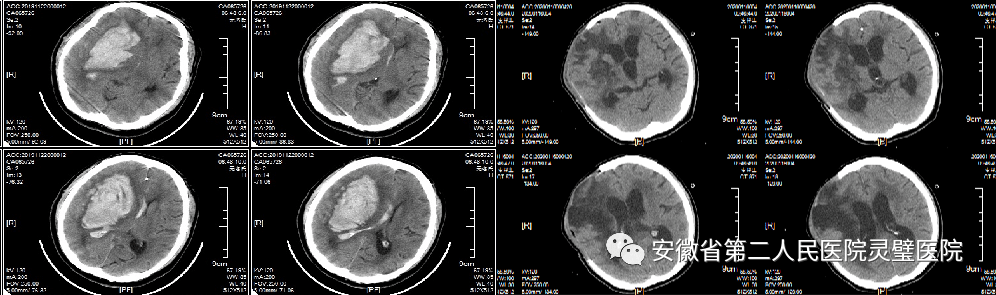

四、脑出血的综合治疗技术

脑出血是临床常见神经重症,原发性高血压是最常见原因之一,根据病人的不同特点,我科形成了从保守治疗、微创治疗到去大骨瓣减压等系列个性化特色技术,临床救治水平达到国内先进水平。

经额穿刺血肿引流术

经颞小骨窗神经内镜下血肿清除术

去大骨瓣减压术+脑内血肿清除术